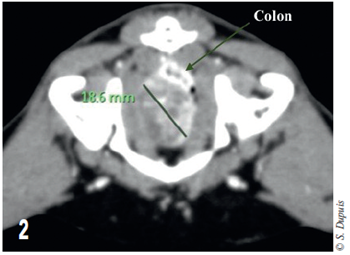

Cette masse déplace le côlon dorsalement à gauche. Elle se trouve à 18 mm de la vessie dorsalement à la symphyse pubienne (figure 2).

Photo 2 – Coupe transversale tomodensitométrique de l’abdomen. Le côlon est déplacé et écrasé dorsalement à la masse